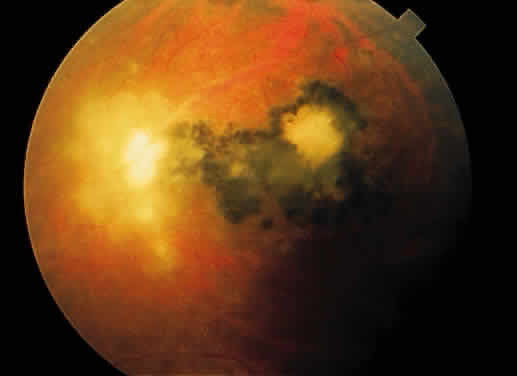

Fig. 13. A. Fundus photograph of a subpigment epithelium hemorrhage superotemporal

to the disc secondary to a macroaneurysm. Notice its dark color and sharp

border. The central portion of the hemorrhage has extended through

the sensory retinal to the subinternal limiting membrane area. B. Fluorescein angiography showing the retinal vessels overlying the deep

hemorrhage but obscured by the central extension anteriorly. (B, courtesy of William Tasman, MD, Philadelphia, PA) Fig. 13. A. Fundus photograph of a subpigment epithelium hemorrhage superotemporal

to the disc secondary to a macroaneurysm. Notice its dark color and sharp

border. The central portion of the hemorrhage has extended through

the sensory retinal to the subinternal limiting membrane area. B. Fluorescein angiography showing the retinal vessels overlying the deep

hemorrhage but obscured by the central extension anteriorly. (B, courtesy of William Tasman, MD, Philadelphia, PA)